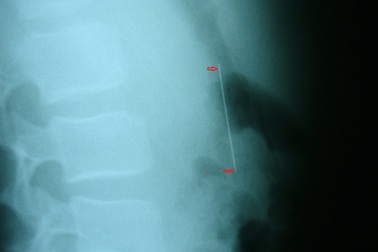

Bé trai 4 tuổi bị chiếc kim gỉ sét đâm xuyên phổiChụp X-quang bệnh nhi, các bác sĩ ở TPHCM phát hiện chiếc kim may vá quần áo đã gỉ sét nằm trong phổi trái của bé trai 4 tuổi.